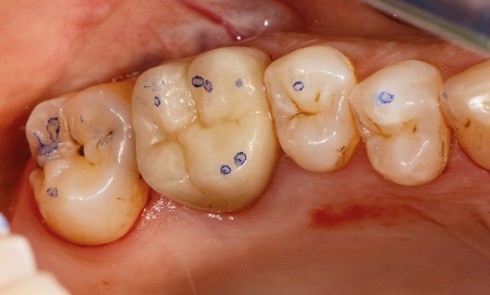

Article réservé à nos abonnés Coronoplasties occlusales préprothétiques

La problématique de l’équilibration préprothétique n’est pas nouvelle : elle a été décrite par Pline l’Ancien 23 ans après J-C....